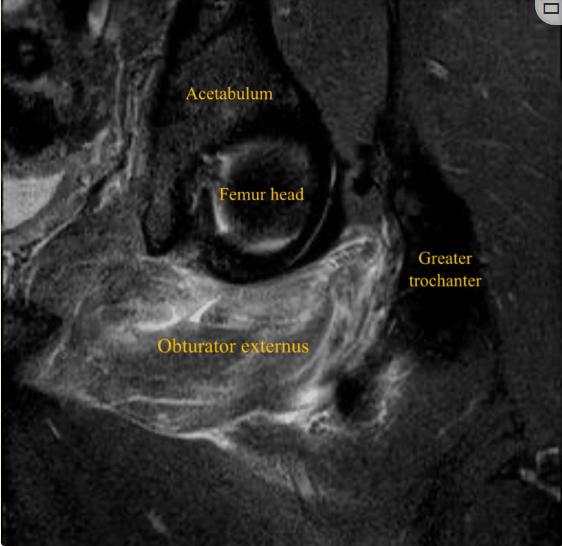

患者男性,32岁,职业足球运动员,在赛季训练期间出现急性左腹股沟疼痛和臀部疼痛,视觉模拟量表(VAS)评分为8/10,这是由髋关节的快速和负重内旋运动引起的,髋关节和膝关节弯曲约90度,在快速改变方向和切入进攻的过程中,功能立即丧失。患者否认腿部有任何麻木、虚弱或辐射性疼痛。体检时,没有瘀伤、瘀斑、水肿或肿胀。坐骨结节触诊有轻微疼痛和压痛。在内收肌、腘绳肌或髂腰肌的特定测试中未发现异常。膝关节和髋关节处于90°时髋关节主动外旋和被动内旋都会引起髋关节疼痛。这位运动员跛行。对左髋关节进行x线检查,以排除髋关节病变,包括股骨髋臼撞击。核磁共振成像显示左侧闭孔外肌的后腱膜下/肌腱膜撕裂,从耻骨起点延伸至外侧肌腱连接处,横断面测量为10 cm,前后径为3.5 cm,伴有股方肌和闭孔内肌间质水肿(图1-4)。

图1、左大腿冠状面 (STIR) MRI显示左闭孔外撕裂